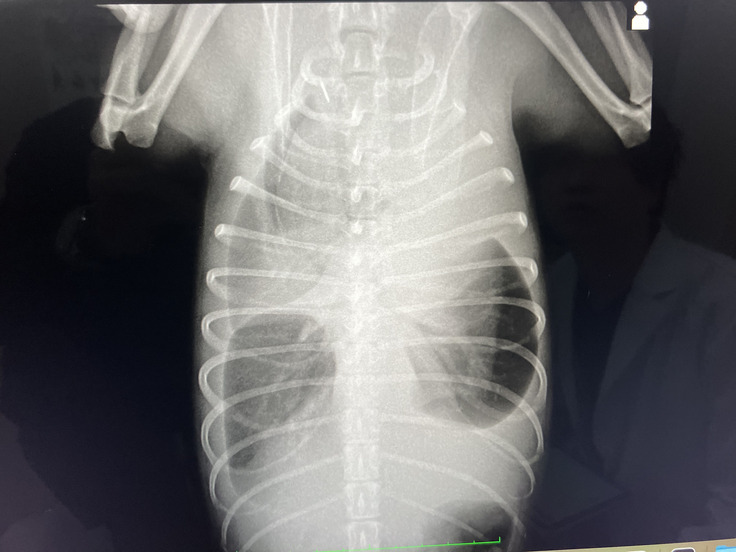

【最初のレントゲン】胸水で真っ白です。そのせいで肺の形までくっきり・・

見比べると非常に改善していることが分かるようになりました。

最初は見えてしまっていた肺も見えなくなり、ほぼ正常な状態になってきました。